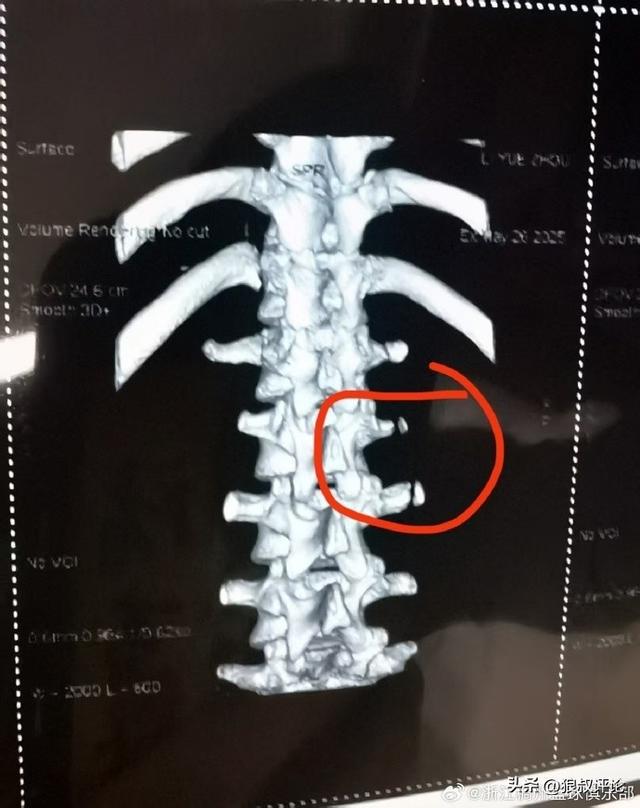

北京时间6月9日,根据浙江男篮官方社交媒体发文:我俱乐部球员李悦洲在5月26日秦皇岛备战U19世青赛训练中不幸遭遇横突骨折,经中国篮协联系北京积水潭医院骨科专家会诊,预计伤停3个月。